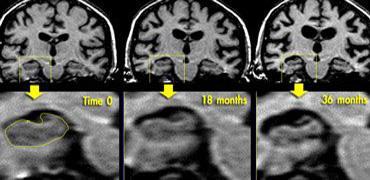

Chuỗi xung T1W mặt phẳng coronal qua hồi hải mã cho thấy teo não tiến triển trong AD gia đình (hình ảnh được cung cấp bởi Nick Fox).

Nếu có nghi ngờ mạnh về bệnh Alzheimer, việc lặp lại khảo sát có thể hữu ích để theo dõi sự tiến triển của tình trạng teo não (thùy thái dương giữa).

Các hình ảnh cho thấy kết quả theo dõi tại thời điểm 18 và 36 tháng ở một bệnh nhân có nguy cơ mắc AD gia đình, minh họa sự tiến triển của bệnh.